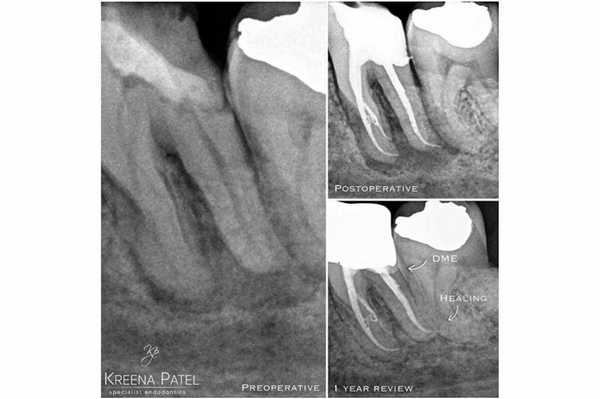

Фото 2. Лечение корневых каналов и формирование композитной культи на зубе LL6. Пациент был направлен к лечащему врачу для изготовления накладки с перекрытием бугров. Золотая накладка была зацементирована на Fuji Plus. Дистальный край находился под десной, а край накладки был сформирован на композитной реставрации (DME). Граница препарирования на всех поверхностях находилась в границах тканей зуба, кроме дистальной поверхности. Рентгенограмма, полученная через год, демонстрирует признаки заживления периапикального поражения.

Фото 7. Пациент обратился за стоматологической помощь по поводу кариеса корня и возможности восстановления зуба LR6. В ходе первого визита был очищен весь кариес и удалена старая пломба, после чего приступили к DME. Эндодонтическое лечение проводили в ходе второго визита. В дистальный канал установили стекловолоконный штифт, а всю дистальную поверхность восстанавливали посредством композита. Пациент был направлен к лечащему врачу для изготовления непрямой реставрации.

DME является полезным клиническим подходом, который эффективно работает в конкретных клинических случаях. Современные данные указывают на то, что непрямые реставрации зубов, предварительно прошедших процедуру DME, демонстрируют успешный результат функционирования на протяжении длительного времени. Во многих случаях DME остается последним шансом восстановления проблемных зубов с глубокими дефектами. Перед началом лечения пациент должен быть проинформирован о всех преимуществах и недостатках подобного алгоритма вмешательства, а также относительно потребности в проведении тщательной очистки проблемных участков с помощью межзубных ершиков, которые обеспечивают поддержку здорового состояния тканей пародонта.